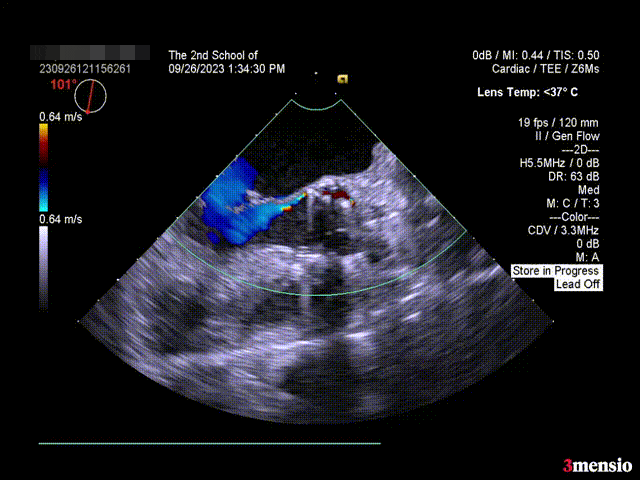

瓣膜释放后超声情况:

短轴超声

长轴超声

术后压差 5mmHg